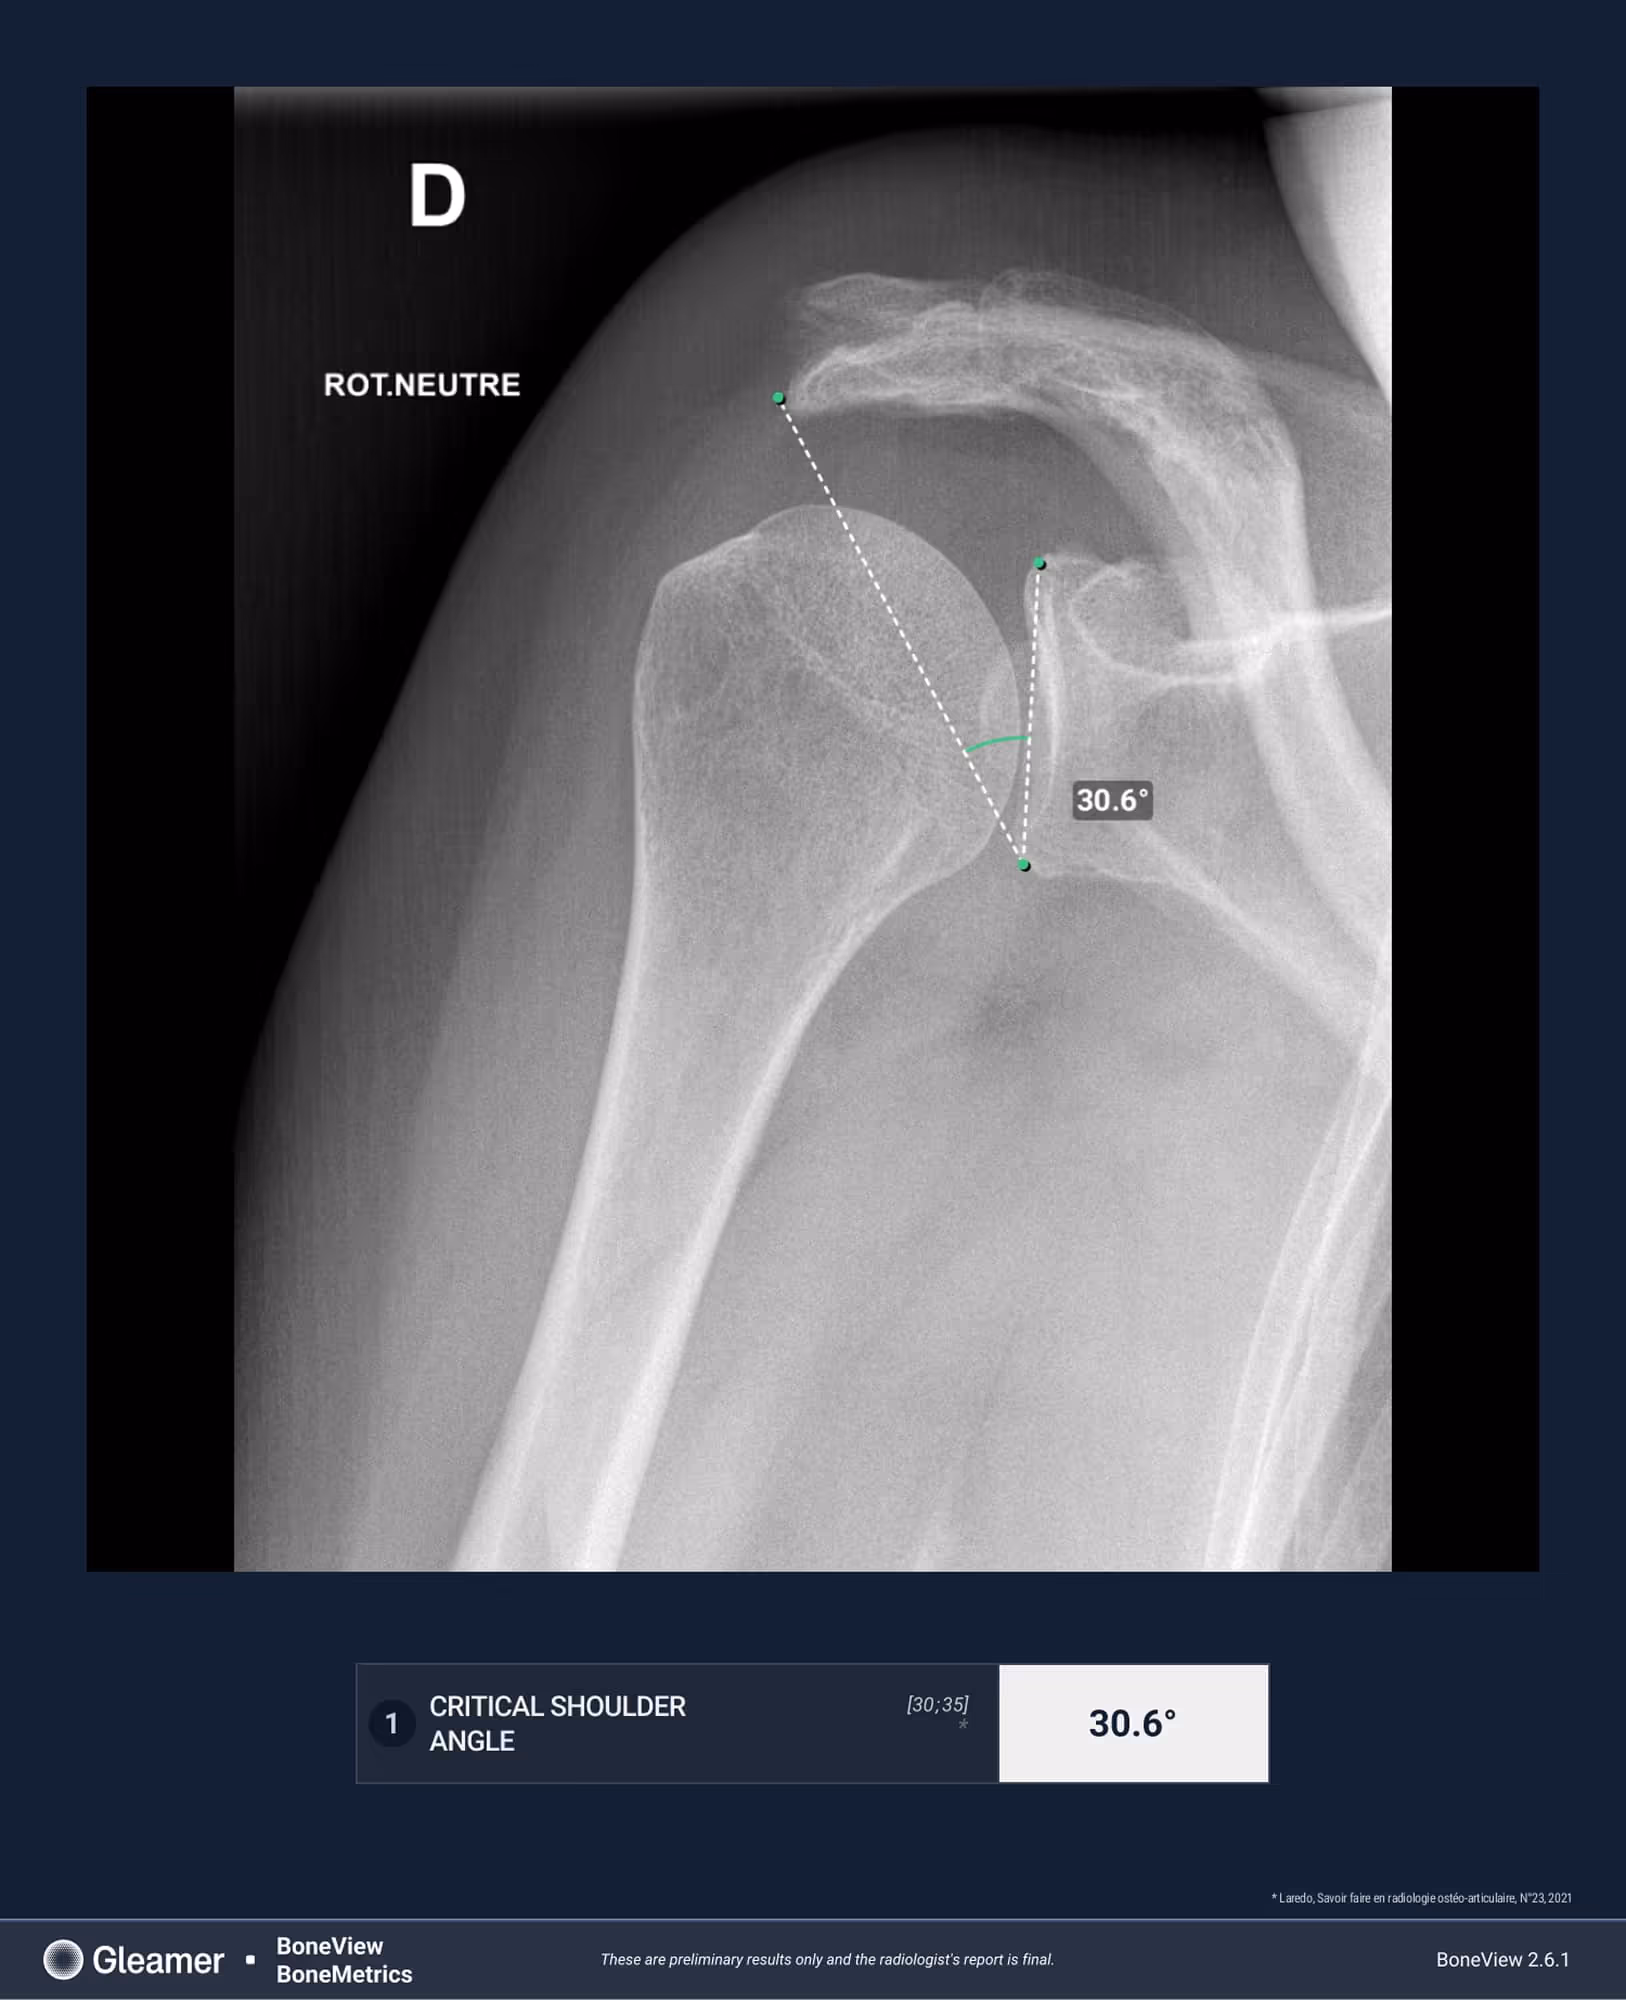

Indication

A 64-year-old female presenting with persistent left shoulder pain, undergoing evaluation prior to potential acromiosplasty.

Results

BoneMetrics found a critical shoulder angle within normal limits.